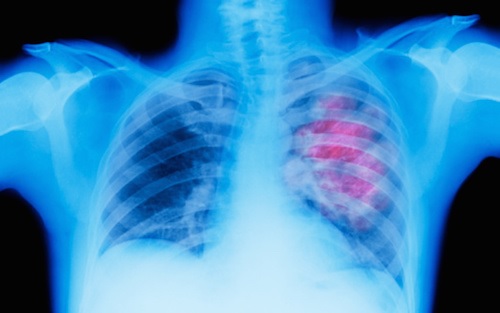

اثر شگفت‌انگیز درمان صبحگاهی در افزایش بقای بیماران سرطان ریه

ICTPRESS - نتایج یک کارآزمایی بین‌المللی نشان می‌دهد که درمان بیماران مبتلا به سرطان ریه پیشرفته در ساعات اولیه روز، طول عمر آن‌ها را به طور چشمگیری افزایش می‌دهد و پیشرفت بیماری را کُند می‌کند.